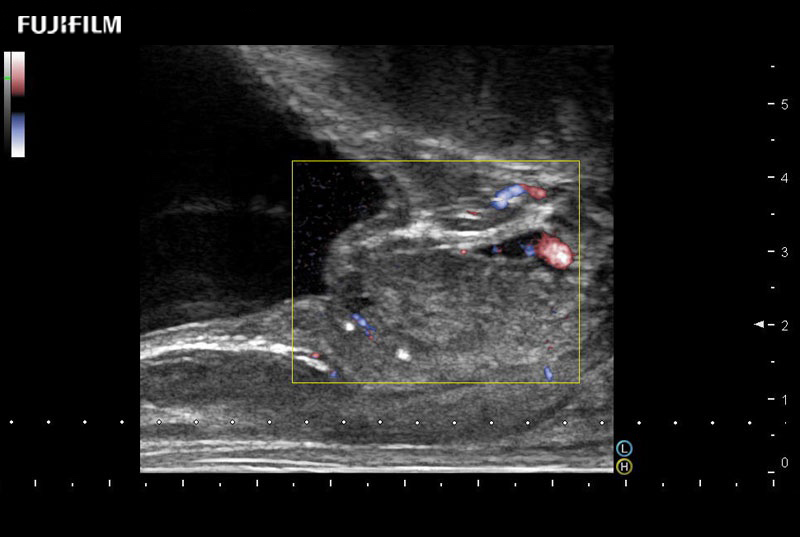

including: B-Mode, Color Doppler, Power Doppler, Fine Flow

– better visualization of tumors to improve understanding of blood flow information

38mm footprint is ideal for scrotal and penile doppler imaging

Larger footprint is ideal for scrotal and penile doppler imaging

Designed for high-resolution imaging of the scrotal and penile regions. This advanced transducer offers exceptional image quality, user-friendly features, and specialized functionalities to support accurate urological diagnostics and enhance patient care.